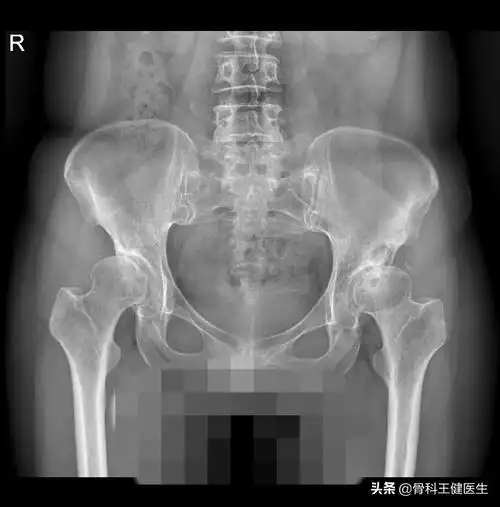

髋关节发育不良继发骨关节炎一例